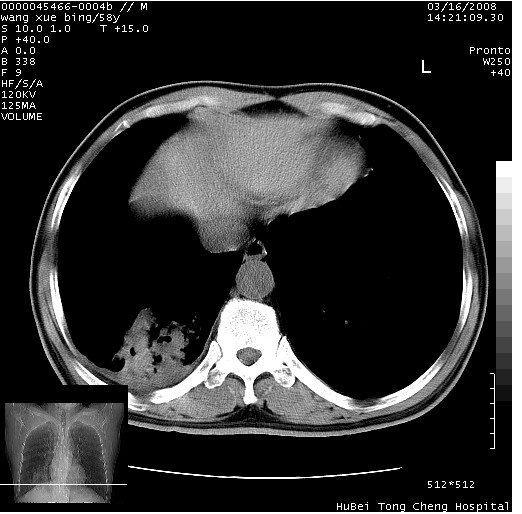

患者 男,58岁。咳嗽、咯血3月余。

胸部cr x线片提示:1)右下肺脓肿。2)右下肺周围型肺癌不排除。建议:行ct扫描检查。

胸部ct轴位平扫(层厚10mm,螺距1.5,重建间隔10mm),图像如下:

右肺下叶团块及不规则空洞,内壁不规则,外缘见粗长毛刺,临近胸膜明显增厚并与病灶关系密切。支持考虑:右肺肺脓肿!建议穿刺病理检查待除外周围型肺癌!

右肺下叶见不规则厚壁空洞,内壁不规则,外缘见粗长毛刺,临近胸膜明显增厚并与病灶关系密切。支持考虑:周围型肺癌!

右肺下叶周围型肺癌伴空洞形成!征象比较明显!分叶、毛刺、胸膜凹陷征、厚壁空洞,壁结节!

空洞壁厚,不规则,其内可见壁结节,周围可见毛刺及阻塞性炎变,多考虑癌性病变.